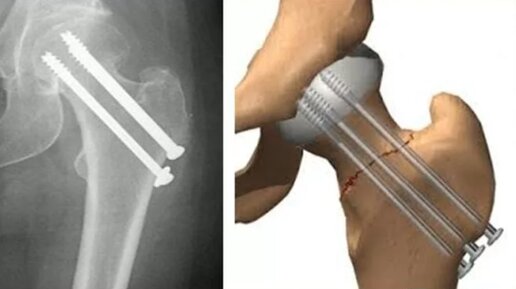

Пластина для лечения переломов и переломо-вывихов акромиального конца ключицы

Переломы ключицы, по данным большинства авторов, составляют 10-19,5% от всех переломов костей скелета. Травматические повреждения связочного аппарата акромиально-ключичного сочленения с вывихами акромиального конца ключицы представляют собой актуальную проблему современной травматологии, составляя от 7,0 до 26,1 % среди всех вывихов костей скелета и более 10% случаев острых травм плечевого пояса, занимая по частоте третье место после вывихов в плечевом и локтевом суставах [1,12]. Частота переломов...